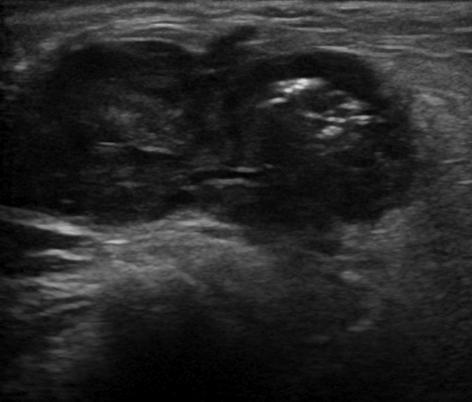

U tuyến nước bọt

» Thông tin: Nam giới – 72 tuổi.

» Lâm sàng: Khối vùng mang tai.

# Ung thư biểu mô tuyến (Adenocarcinoma).